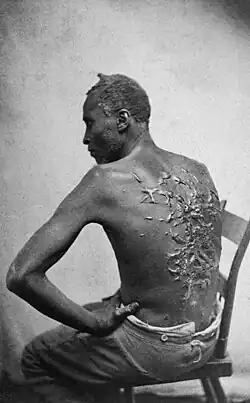

The famous American Civil War-era photograph "Whipped Peter" depicts an escaped former slave with extensive keloid scarring as a result of numerous brutal beatings from his former overseer.